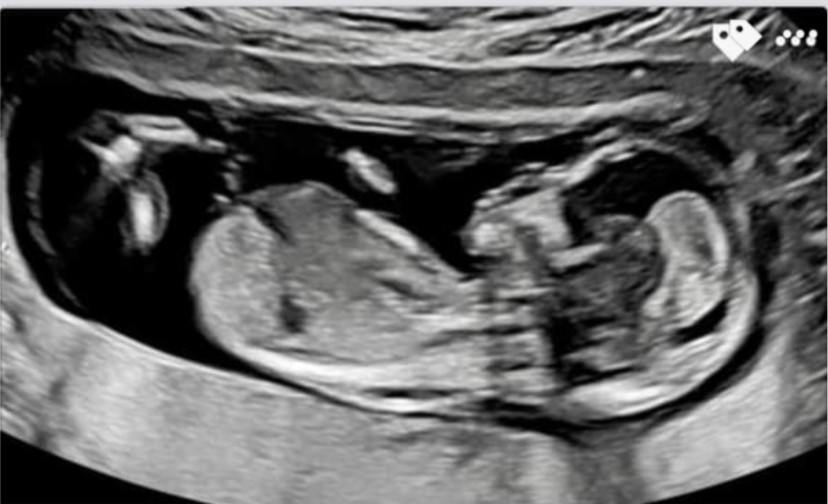

13 week and 16 week scan...Is this possibly a GIRL???

Just wondering if there is anything to be seen in these images from 13 weeks and a 16 week bladder shot but not sure if it shows gender around the potty region.

Would appreciate Atomics opinion on these, thank you!!!Attachment 43253Attachment 43254Attachment 43255Attachment 43256Attachment 43257Attachment 43258Attachment 43259